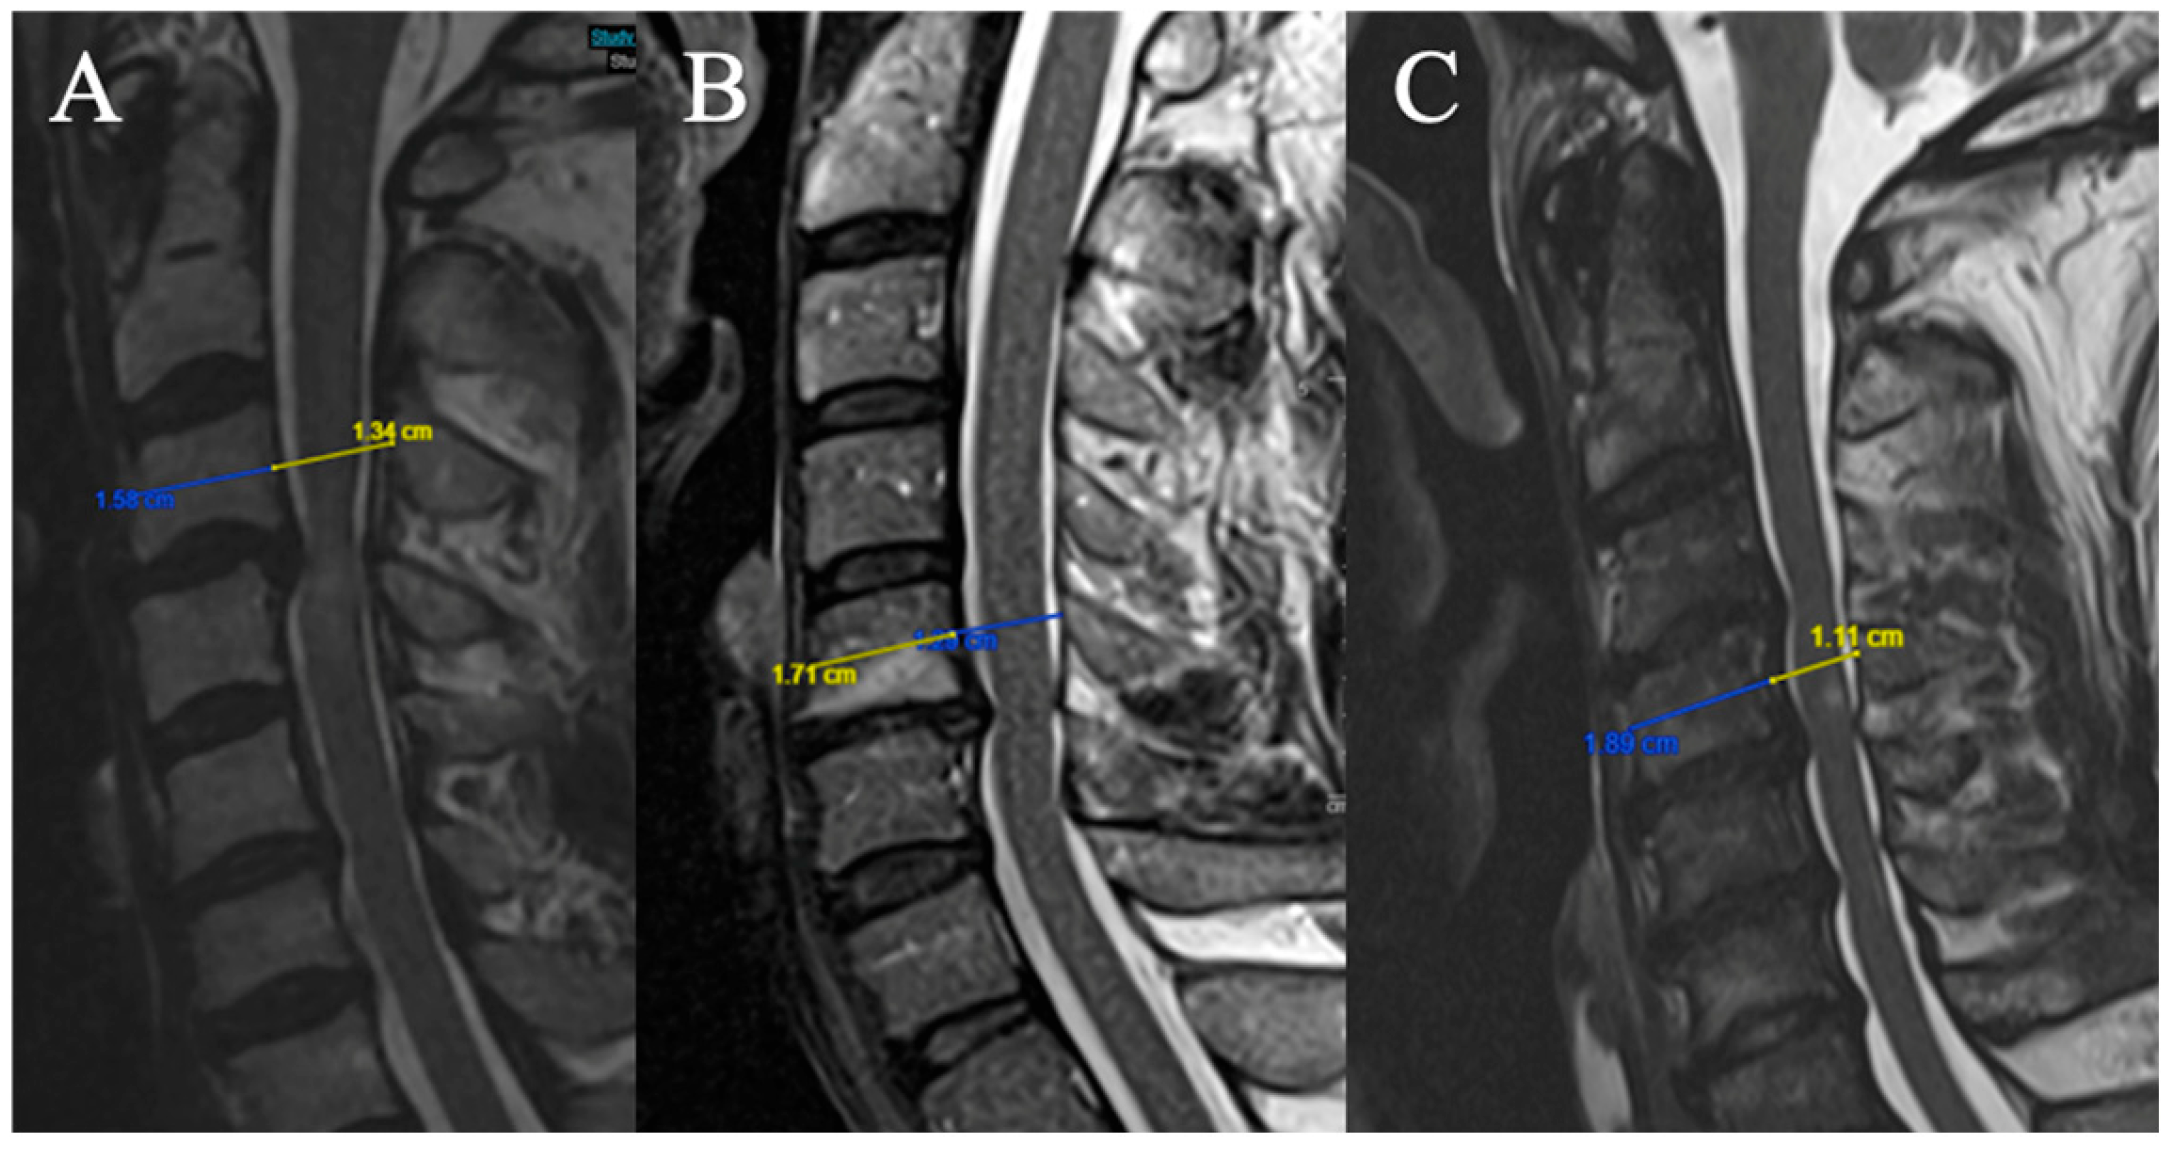

The FR is defined as the ratio of the anteroposterior diameter of the spinal cord to the transverse diameter on an axial slice at maximum compression on T2-weighted sequences (Figure 1).

Three grades were selected on a sagittal slice (Figure 2):

Figure 2. (A) No T2HI; (B) focal T2HI; (C) multifocal T2HI.